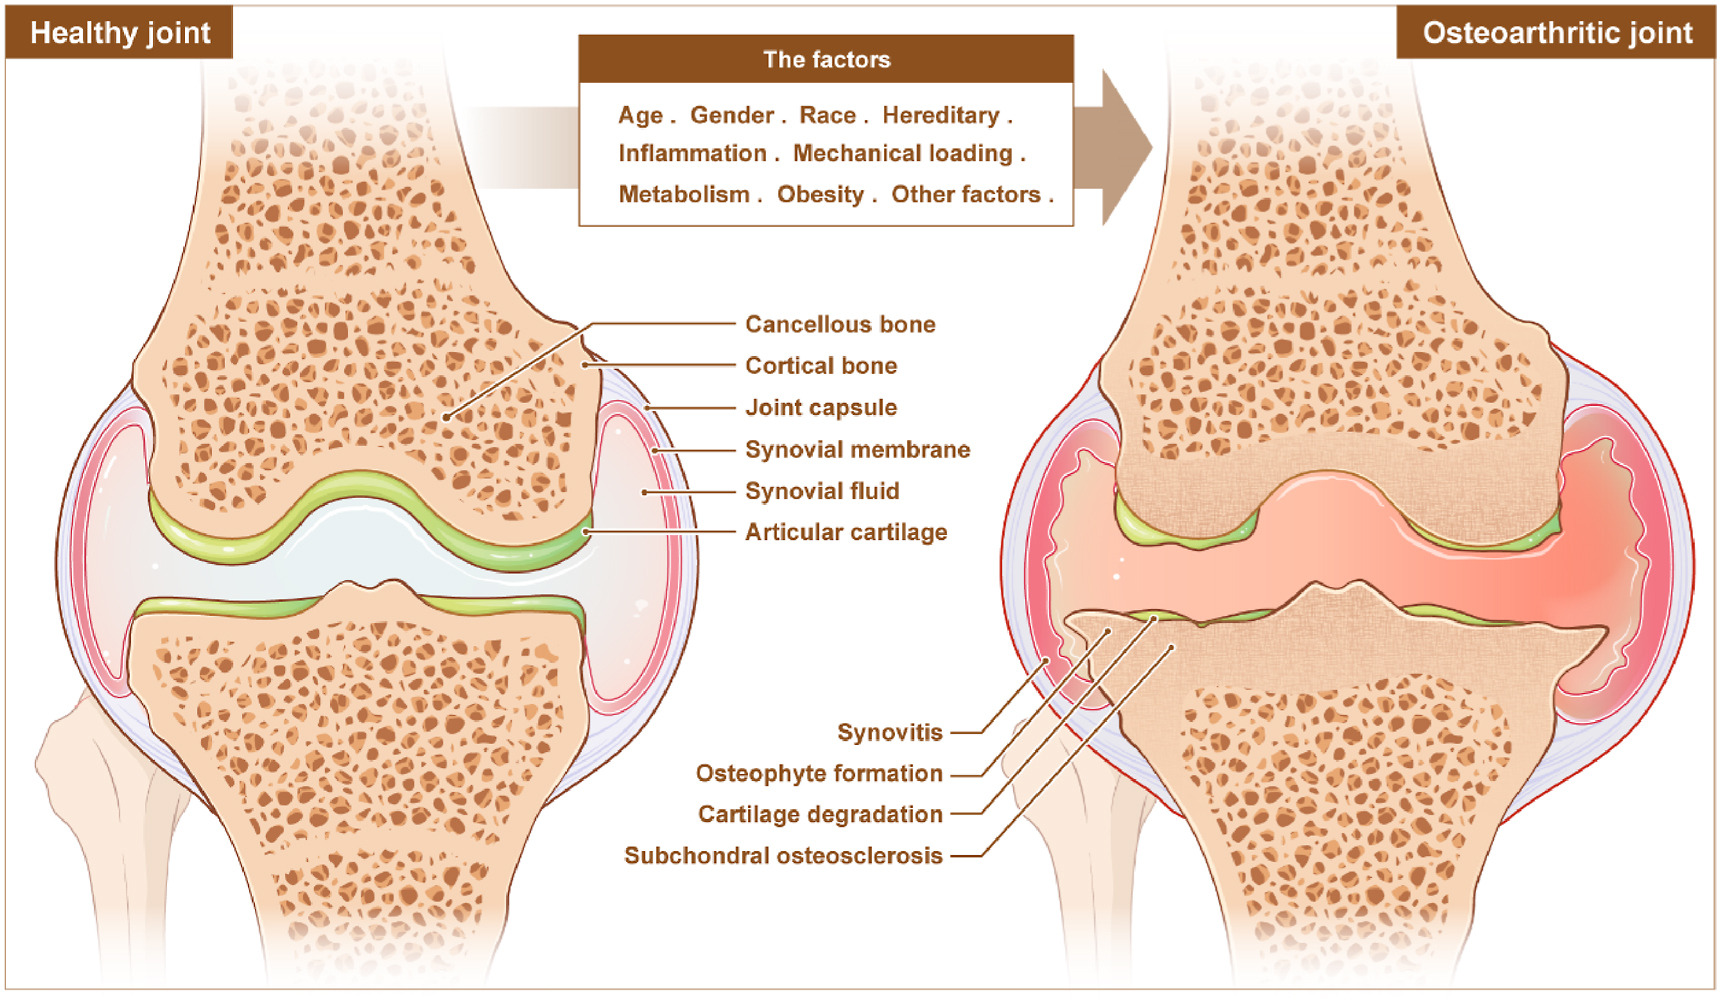

For decades, doctors dismissed osteoarthritis as inevitable wear and tear. But groundbreaking 2024-2025 research from Nature Reviews Rheumatology proves this “joint disease” actually starts in your bloodstream.

The Paradigm Shift: Why Osteoarthritis Is Now Called a Systemic Disease

Doctors used to think osteoarthritis came from joints wearing out. Like tires on a car. But December 2025 research in Nature Reviews Rheumatology proved them wrong.

Here’s the evidence that changed everything. Obese people get hand and wrist arthritis. These joints don’t bear weight. If OA was just mechanical wear, this wouldn’t happen. But it does. This proves metabolic factors matter more than we thought.

The numbers tell the story. 52% of people with type 2 diabetes develop OA. Only 27% without diabetes get it. That’s not a coincidence. Right now, 595 million people globally have OA. By 2050, that number hits 1 billion. Your risk goes up 35% for every 5-point increase in BMI.

A systemic disease affects your whole body, not just one spot. Osteoarthritis is now officially in this category. Your bloodstream carries inflammatory signals to all your joints. This is why understanding OA as a systemic disease matters. It opens up new treatment options you’ve never heard about.

The Vicious Cycle: How Metabolic Syndrome Accelerates OA Progression

Metabolic syndrome includes obesity, high blood sugar, bad cholesterol, and high blood pressure. Each component damages your joints. Together, they create a cycle that feeds itself.

Insulin resistance doesn’t just affect diabetes. It affects your joints too. Type 2 diabetes causes damage through oxidative stress and chronic inflammation.

Studies on diabetic mice showed increased cartilage damage and synovial inflammation after just 10 weeks. Human patients with diabetes report worse pain on WOMAC scores—a standard arthritis pain measurement.

Here’s the cruel cycle. Joint damage makes you less active. Less activity worsens insulin resistance. Worse insulin resistance creates more inflammation. More inflammation damages joints further. This bidirectional relationship makes treatment harder.

Why Your Hand Arthritis Proves It’s Not Just Weight:

Hand osteoarthritis in obese people proves mechanical loading isn’t the whole story. Your hands don’t carry your body weight. But metabolic factors in your bloodstream reach ALL joints. This is why controlling your metabolism matters more than you think.